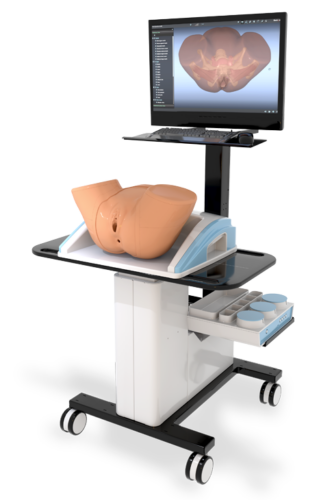

The World's Most Sophisticated Pelvic Simulator

No other pelvic anatomy and pelvic exam simulator provides the PELVIC Mentor’s level of realism and accuracy.

As a strong didactic tool, the PELVIC Mentor provides trainees with immediate feedback on anatomical recognition and the opportunity to practice pelvic exams accurately. The unique combination of the model’s anatomical structure, finger sensation and virtual model provide the most effective training tool to date, aimed at developing the physician’s confidence during pelvic examinations.

The PELVIC Mentor allows nurses, nurse practitioners, Doctorate Of Nursing Programs (DNP), certified nurse midwives, OB/GYNs, family practice doctors, physician assistants, medical students, and physician assistant learners to obtain detailed knowledge of pelvic anatomy and to acquire the comprehensive skills required to perform pelvic exams.